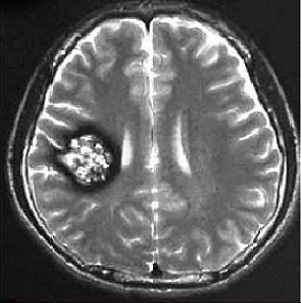

腦海綿狀血管瘤是一簇異常血管,通常在腦和脊髓中發(fā)現(xiàn)。其涉及一組血管的異常擴(kuò)張。由于這種擴(kuò)張,在受影響的血管中形成稱(chēng)為洞穴的氣泡狀空腔。通過(guò)這些洞穴的血液流動(dòng)減慢,并且血管壁在這些斑點(diǎn)處特別弱。因此,血管壁有可能被損壞并導(dǎo)致出血。由于這些具有洞穴的擴(kuò)張血管呈簇狀并且往往呈現(xiàn)紅色或紫色,其外觀有些像紫色的漿果或者爆米花樣外觀。腦干海綿狀血管瘤是指生長(zhǎng)在腦干(包括延髓、中腦、橋腦等部位)的顱內(nèi)海綿狀血管畸形。

1、核磁共振(MRI):在顱內(nèi)海綿狀血管瘤的診斷中檢出率均較高,均具有較為典型的影像學(xué)表現(xiàn)